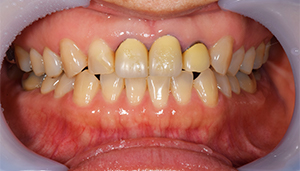

症例2

治療前

治療後

治療内容

奥歯はアマルガムという発ガン性があると言われている銀の素材を金銀シルバーインレーに変えました。前歯は金属を使用した歯でややまわりのご自身の歯より色がういていたので、周りの歯にあわせて透明感のある仕上がりのある材料にてやり変えました。

治療期間 1ヶ月

治療費 合計:990,000円 (内訳)

ジルコニアボンド:165,000円×6本

治療のリスク・副作用 被せ物を外すと、ご自身の歯が少ない場合は別途はを残すための処置が必要になることがあります。